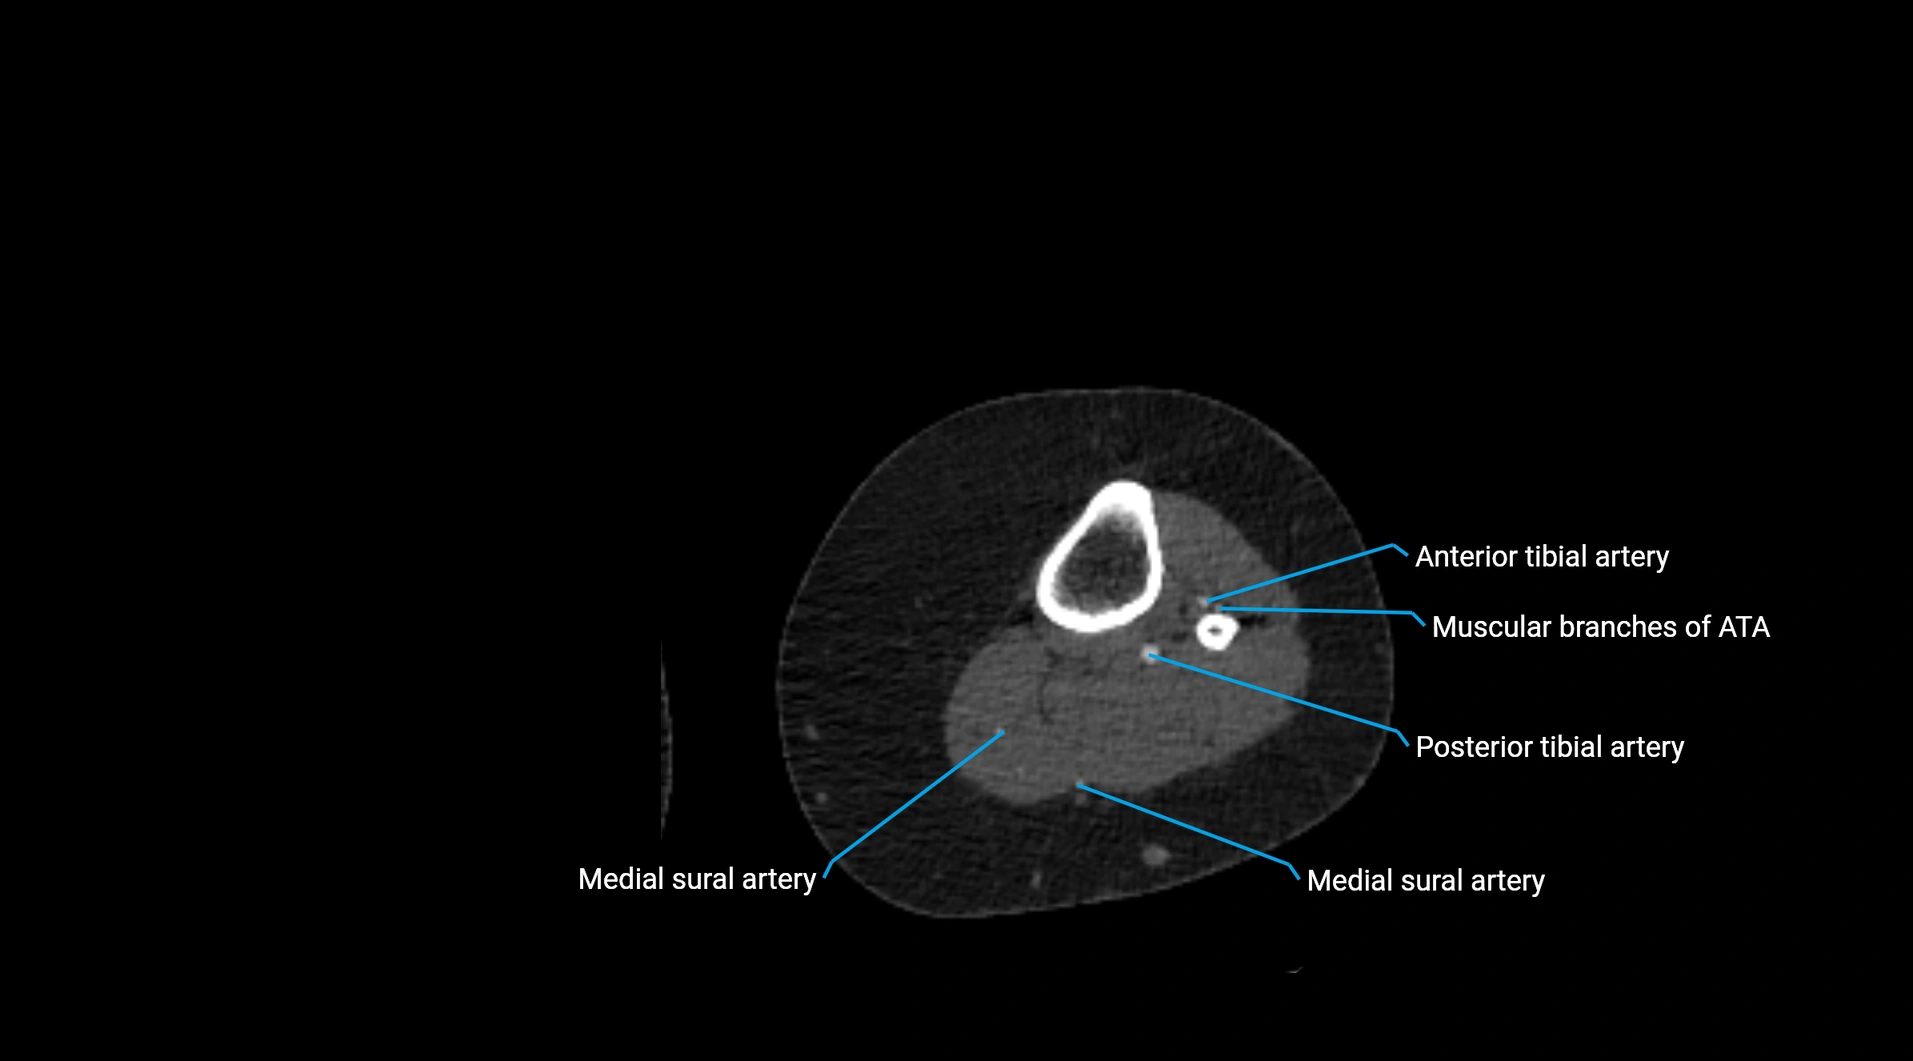

CT images

image